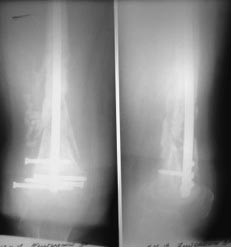

Пациентка 72 лет, сочетанная травма в июле 2011. Одно из повреждений (кроме ЧМТ, грудной клетки, длительной реанимации) перелом дистального бедра.

После временной фиксации в аппарате через 3 недели накостный остеосинтез. Раннее нагноение, попытки консеравативного лечения. Под наше наблюдение попала через 6 месяцев, гнойный свищ по наружной поверхности бедра, до пластины, нестабильная фиксация,миграция винтов, боли, постельный режим. Первым этапом удалена пластина, некрэктомия, бусы из цемента с а\б, апааратная фиксация. Заживление первичное. Вторым этапом снятие аппарта через месяц, замена бус, интрамедуллярный остосинтез, в последующем (через 1,5 месяца) бусы удалены, введены дополнительные винты из-за начинающейся миграции. Заживление первичное. В настоящее время 7 месяцев после последнего вмешательства, гвоздь динамизирован. На фоне улучшения общего состояния (пациенка активизирована, ходи с доп.опорой, болевой синдром незначительный) сохраняются эпизоды гипертермии проходящие на фоне а\б широкого спектра (авелокс). Р-граммы в динамике - отсутствие признаков нестабильности, резорбции, динамизация не исчерпана.Основная проблема - гипертермия, возобновляющаяся через 2-3 недели после прекращения а\б. Варианты:1) Наблюдать до 12-18 месяцев надесясь на консолидацию с последующим удалением 2) некрэктомия? 3) Резекция в пределах здоровых тканей с онкологическим протезом? Другие варианты